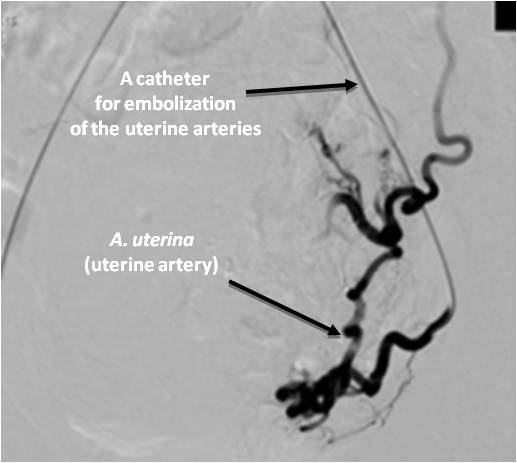

In the endovascular intervention in UL, special attention is paid to the segment of the uterine artery that ascends towards the uterine-tubal angle and gives off numerous tortuous branches directly to the uterine body and cervix (the zone of direct branching of the uterine artery into the terminal branches) (Figure 2).

Fig. 2. A selective angiogram of the left uterine artery of a female patient Z., 40 years, after embolization with preservation of the isthmic and vaginal branches.